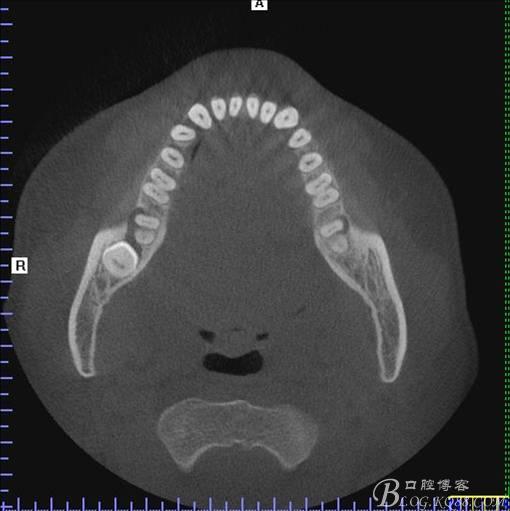

二、術(shù)前CBCT影像:

圖4.水平方向48與47之間的關(guān)系